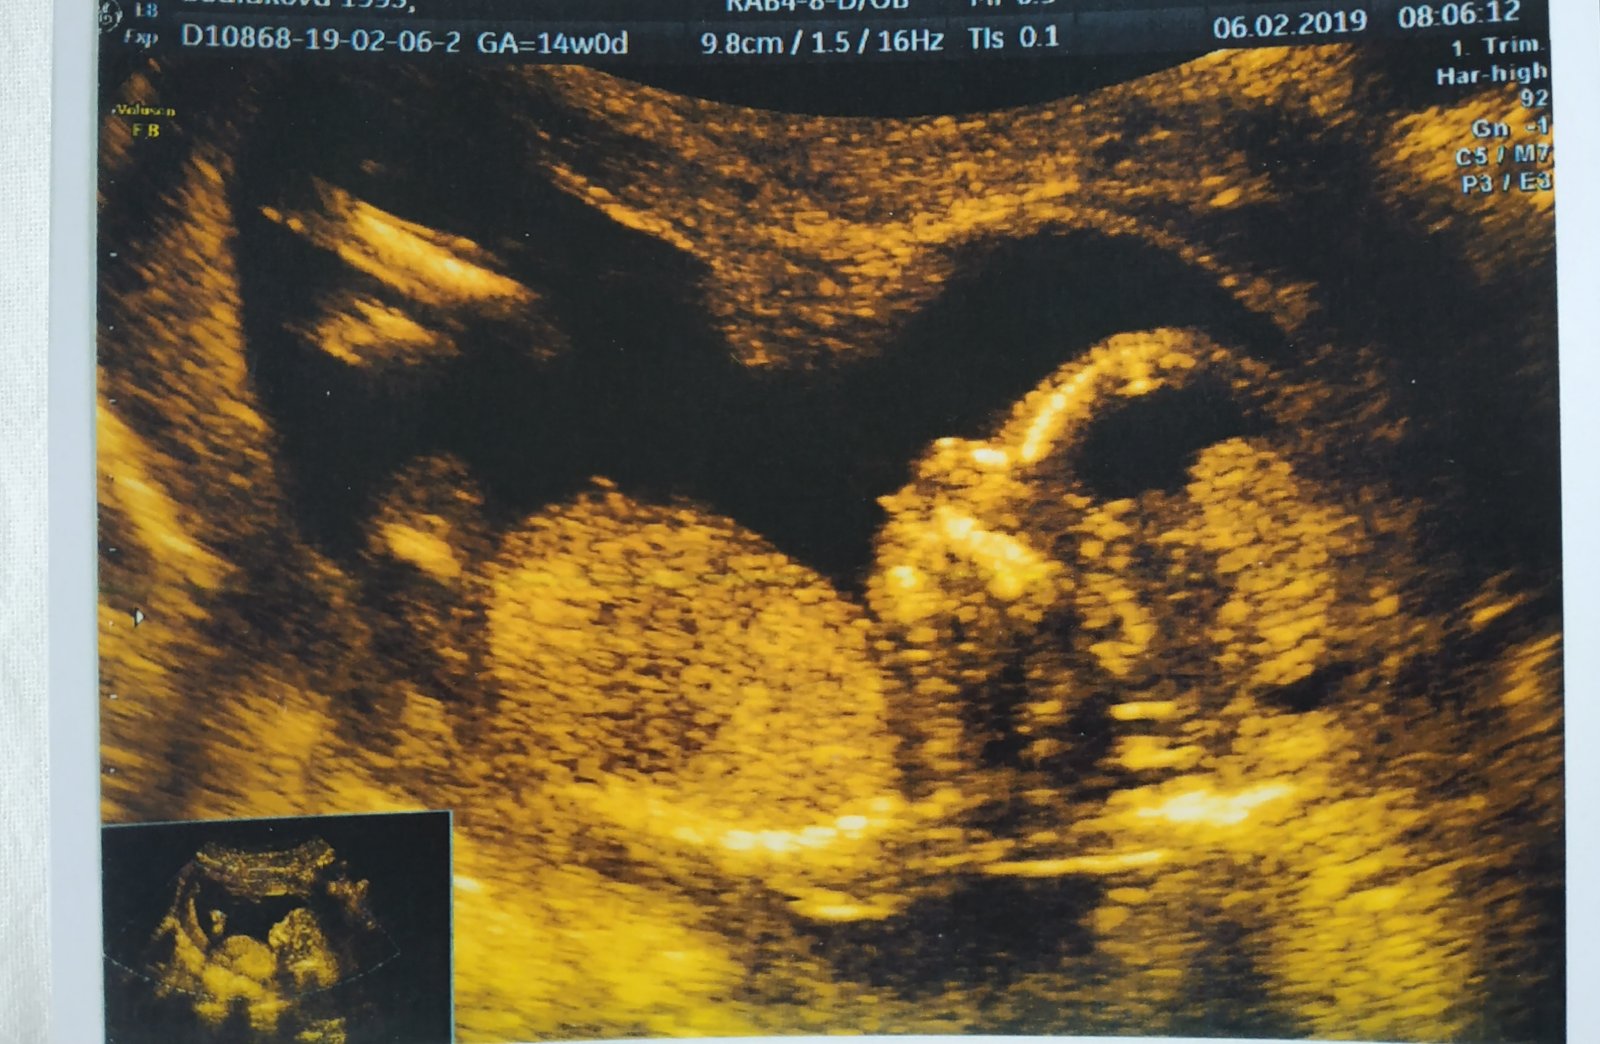

Maminky tak dneska klasická kontrola v poradně opět nejspíš recen kluk , ale neposeda mění polohy v st screening tam snad potvrdí. Myslíte , že toto je pindík? Divná fotka vím na přání pro tatínka 😆, aby viděl že prcek ma dlouhé nohy a po mě určitě ne😆 manžel má 196cm já 164. Co myslíte maminky je to pinďourek?

@slunicko1551 ahoj bohužel nevidím to máš z Veveří z Prenatalu? My čekáme stoprocentně podle pana doktora Vlašina a dle mého gynekologa kluka třeba najdeš podobnost, ale pindík u nás byl viděn vícekrát na snímku to taky nepoznám v této poloze. Já u toho mého kluka vidím jen pokrčené nohy

ahojte, já byla na screeningu v 12+3 a doktor se snažil odhadnout pohlaví podle pohlavního hrbolku, který prý když je rovnoběžně s páteří (?) tak to spíš svědčí o holce a když trčí směrem nahoru tak to bude kluk. nejdřív se mu to zdálo jako holka, ale kluk by to taky prý ještě mohl být :D nicméně to taky odhadoval z tohoto pohledu (jako je tady na fotce) ne toho "mezinožního spodního" :D tak jsem pak pátrala na netu a našla jsem tady tu stránku http://www.ingender.com/forum/forum.aspx?ID=95 kde lidi dávají fotky z 13. týdne po tom, co už mají potvrzené co skutečně čekají. Tak jsem prohlížela holky a říkám si no tak to je jasná holka, nevím co ten doktor řešil. No a pak jsem otevřela kluky a zjistila jsem, že to vypadá úplně stejně :D takže já si ještě počkám na verdikt 🙂

@slunicko1551 u nás pindik trčel už asi v 11.tydnu doktor řekl nejspíš kluk pak se stalo , že na dalším klasickém v pondělí viděl opět a pak na screeningu mě doktor doslova nadal😀, že když jsem se zeptala na pohlaví ,,Vy Jste nedávala pozor? '' a šup pinďourek jak Brno

@lucinkamarecek Pan doktor Marek je moc fajn, já s ním byl vždy spokojená, je moc příjemný a vše krásně vysvětlí... pohlaví mi teda nikdy neřekl, ptže utz mi dělal jen v 8tt, pak už jen poslouchal srdíčko... Já tam jdu zítra. Jinak dneska v Prenatalu u Vlašína - moc toho sice nenapovídá, ale ukáže a sdělí vše podstatné, je vidět, že je to opravdu profík, bylo to rychlé, přesně věděl kdy, jak moc a kam s tou sondou pohnout, nic nemusel složitě hledat (což, rozhodně nemůžu říct o doktorce, která mi screening dělala u malé, té všechno trvalo hrozně dlouho, byla strohá a nepříjemná)... Když jsem ho poprosila, jestli by se podíval na pohlaví, tak nejdřív přes to přejel, že to problesklo tak na vteřinku - hned mi proletělo hlavou, že jsem zahlídla pindíka 😃 ale říkala jsem si, že to třeba mohla být pupeční šňůra, takže na otázku "Tak co, pochválíme tatínka?" jsem neodpovídala... pak prý, "No, v každým případě určitě pochválíme, že? Tak co myslíte" a najel tou sondou přesně na rozkrok - to už nebylo pochyb - kluk jak vyšitej... I přítel to poznal, tak hned nadšeně "Joo, je tam pinďour!" a doktor jen "Přesně tak - pinďour!" 😅😅😅